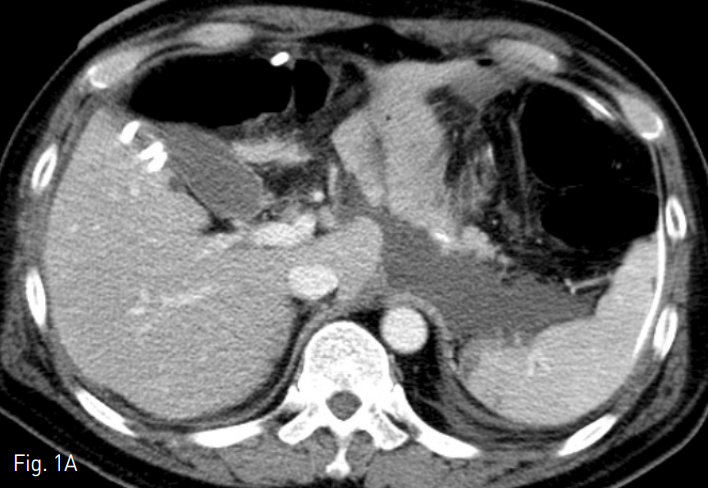

수술 후 10일 째에 시행한 전산화단층촬영에서 식도 소장문합부위 하방과 췌장후방구역, 십이지장 절단 끝의 앞쪽으로 구획화된 액체 저류가 있고 오른 결장주위 공간으로도 액체저류가 있음. 해당 액체 저류들은 미약한 조영 증강이 동반되어 있어 감염된 액체 저류의 가능성이 있고, 이와 같은 소견은 식도소장문합부위 또는 십이지장 절단 끝의 누출 가능성을 시사하는 소견임 (Fig. 1).

Fig. 1

A-B. Contrast-enhanced axial CT scan shows localized fluid collection in extent of inferior aspect of esophagojejunostomy site, retropancreatic area, anterior aspect of duodenal stump, and right paracolic gutter.